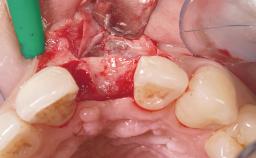

Immediate Flapless Placement of an Implant in a Maxillary Left Central Incisor Site

A 29-year-old female patient presented for treatment to replace the upper left central incisor tooth with an implant- supported restoration. The tooth had been intermittently symptomatic for the previous 12 months. The tooth had originally suffered trauma about 15 years previously. Several endodontic treatments had been performed, including an apicectomy procedure to retain the tooth. The patient was healthy and a non-smoker. She had reasonable expectations in regard to esthetic outcomes and the risk of marginal tissue recession following treatment. At medium smile, the gingival margins of the upper teeth were visible, with a display of 3 to 4 mm of the gingival margins. Gingival recession of tooth 21 and a discrepancy in the gingival levels between teeth 11 and 21 was observable during normal speech and smile.

| Socket Integrity | Damage to one or more bone walls |

| Bone Volume | Damage to one or more socket walls |

| Esthetic Risk | Medium |

| Risk of Complications | High |